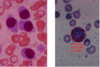

Acute Promyelocytic Leukemia (M3 AML)

M4/5 AML

Chronic Lymphocytic Leukemia (CLL)

Chronic Lymphocytic Leukemia (CLL)

Hairy Cell Leukemia

Hairy Cell Leukemia

Hairy Cell Leukemia